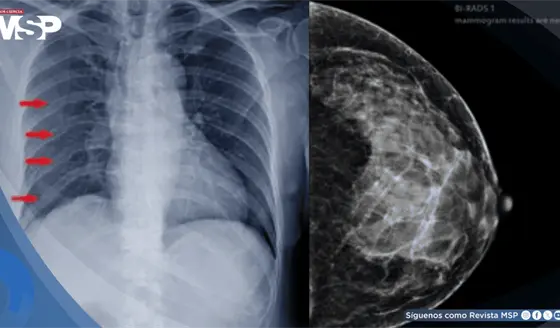

Múltiples fracturas costales por osteorradionecrosis como secuela de la reirradiación por cáncer de mama